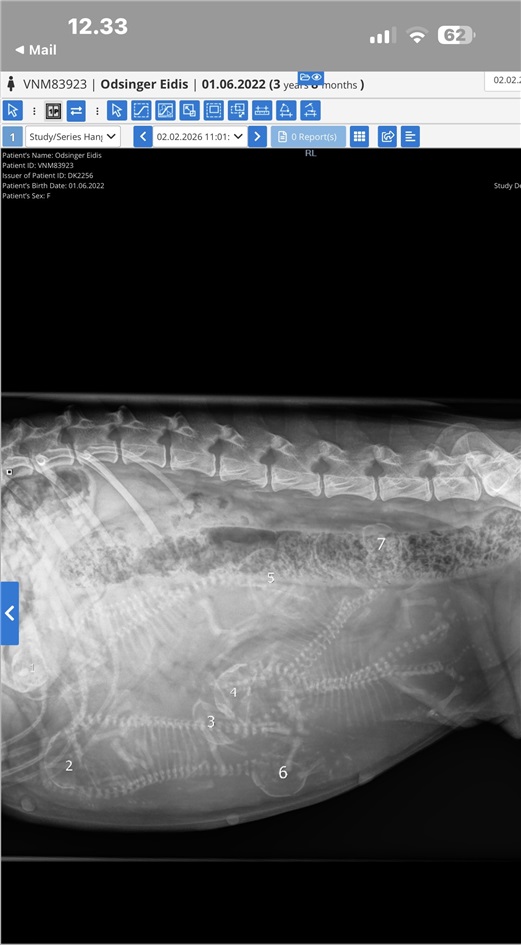

Eydis venter 7 hvalpe!

Røntgen viste 7 hvalpe!

Så er der kun godt en uge til at Eydis føder sine hvalpe. Alt så rigtig fint ud hos dyrlægen, så vi glæder os rigtig meget!